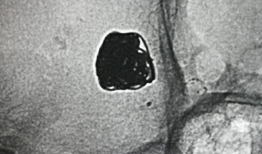

支气管镜检查,一场与呼吸的亲密对话想象你的呼吸系统就像一座神秘的迷宫,而支气管镜检查,就是一把开启这扇神秘之门的钥匙。今天,就让...